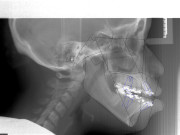

Prediction and Preoperative Workup with Model Surgery

The surgical team spends much time and energy in collaboration with the orthodontist to plan the surgery.  A joint treatment plan is devised.  The orthodontist sets up for the surgery with braces.  The surgical team then plans the surgery using xrays to predict the movements, performs the surgery on models, then fabricates acrylic splints to guide the surgical team in the operating room.